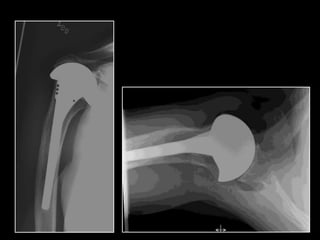

DESIGNS

SURGICAL TECHNIQUE

https://www.vumedi.com/video/reverse-total-shoulder-arthroplasty-technical-

note-and-results-at-uf/